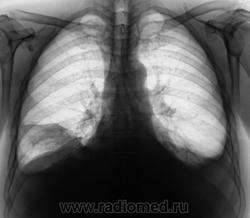

Динамика через 3 дня.

Плевральной пункции не было. Проводилась противовоспалительная терапия по поводу "пневмонии", но пациент, вдруг, "затяжелел"

За три дня, следовательно, 0,5 л жидкости слева ушло.....а справа резко прибыло ...как будто только диафрагмы, но без значительного прибавления жидкости...Интересно....печень же за три дня так не увеличиться...

Поскольку такой внезапный парез диафрагмы маловероятен...смею предположить наличие базального плеврита справа...он же - диафрагмальный плеврит. Здорово бы было посмотреть на УЗИ - за три секунды решили бы проблему.